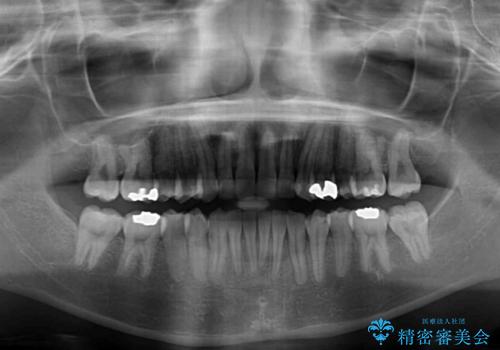

矯正治療後には、目立つ銀歯と隣接するむし歯をセラミックインレーにて修復治療することとしました。

左右ともに奥歯の咬み合わせには大きな問題がなく、窮屈な歯列を解決すれば歯列を整えることできたため、僅か1年で終えることができました。